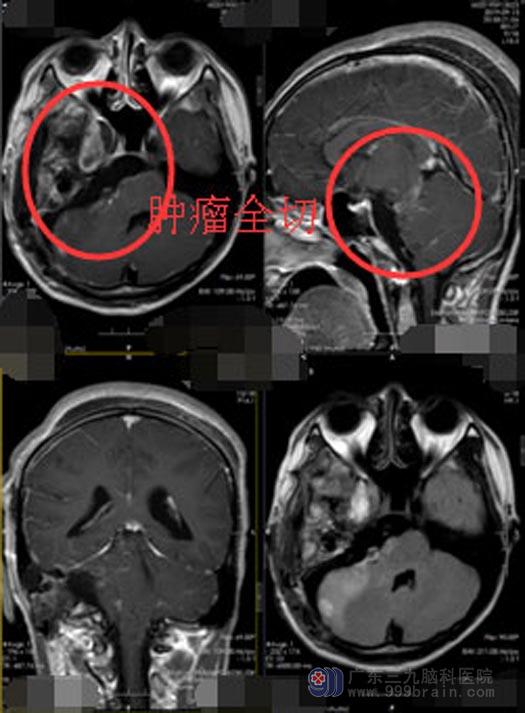

鲁明副院长带领神经五科医生团队经过缜密的术前讨论,决定采用乙状窦后联合颞下入路切除。乙状窦后入路见肿瘤位于右侧桥小脑角,与面听神经粘连严重并被三叉神经包裹,显微镜下分块切除,中后颅窝组神经保留完整,肿瘤和脑干粘连严重,予肿瘤全切;再从颞下入路见肿瘤主要位于中后颅窝底,切口三叉神经半月节可见肿瘤,考虑是肿瘤起源,给予分块切除,肿瘤突入海绵窦内给予肿瘤全切。术中对颈内动脉,后交通动脉,动眼神经保护完整,手术顺利完成,未出现手术损伤。病理结果:非典型神经鞘瘤。